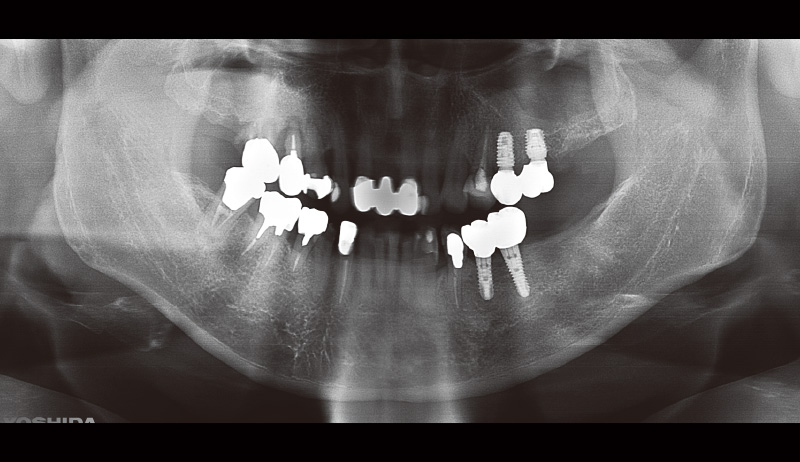

29歳男性、主訴:左下の奥歯が痛い。

₆の歯根破折による痛みがあり抜歯即時埋入を行った。φ6.0長さ8.0mmのSPIイニセルインプラント エレメントRCを選択(図3, 4)。埋入後3か月目で印象を行い補綴装置をセットした。抜歯即時埋入治療でも使いやすいインプラントだと実感した(図5)。

![[写真] 初診時のパノラマX線写真](/academic/dentalmagazine/wp-content/uploads/sites/2/2025/09/194-8_photo03.jpg)

図3 初診時のパノラマX線写真 -